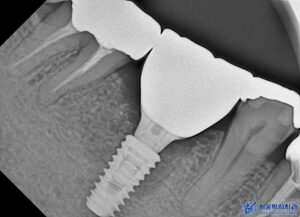

그 다음 치료는 오른쪽 아래로,

CT상에서도 보이는

뿌리 끝 염증과 충치로 인해

골소실이 진행될만큼

썩어있는 상태였습니다.

이후 무절개임플란트 식립을 하였으며,

뒤 치아는 재보철 수복을 해드렸습니다.

왼쪽 위가 마무리 된 후

이어서 아래쪽도 서울박사치과의 맞춤형 지대주와

최종 보철을 제작하여 맞춰보았습니다.